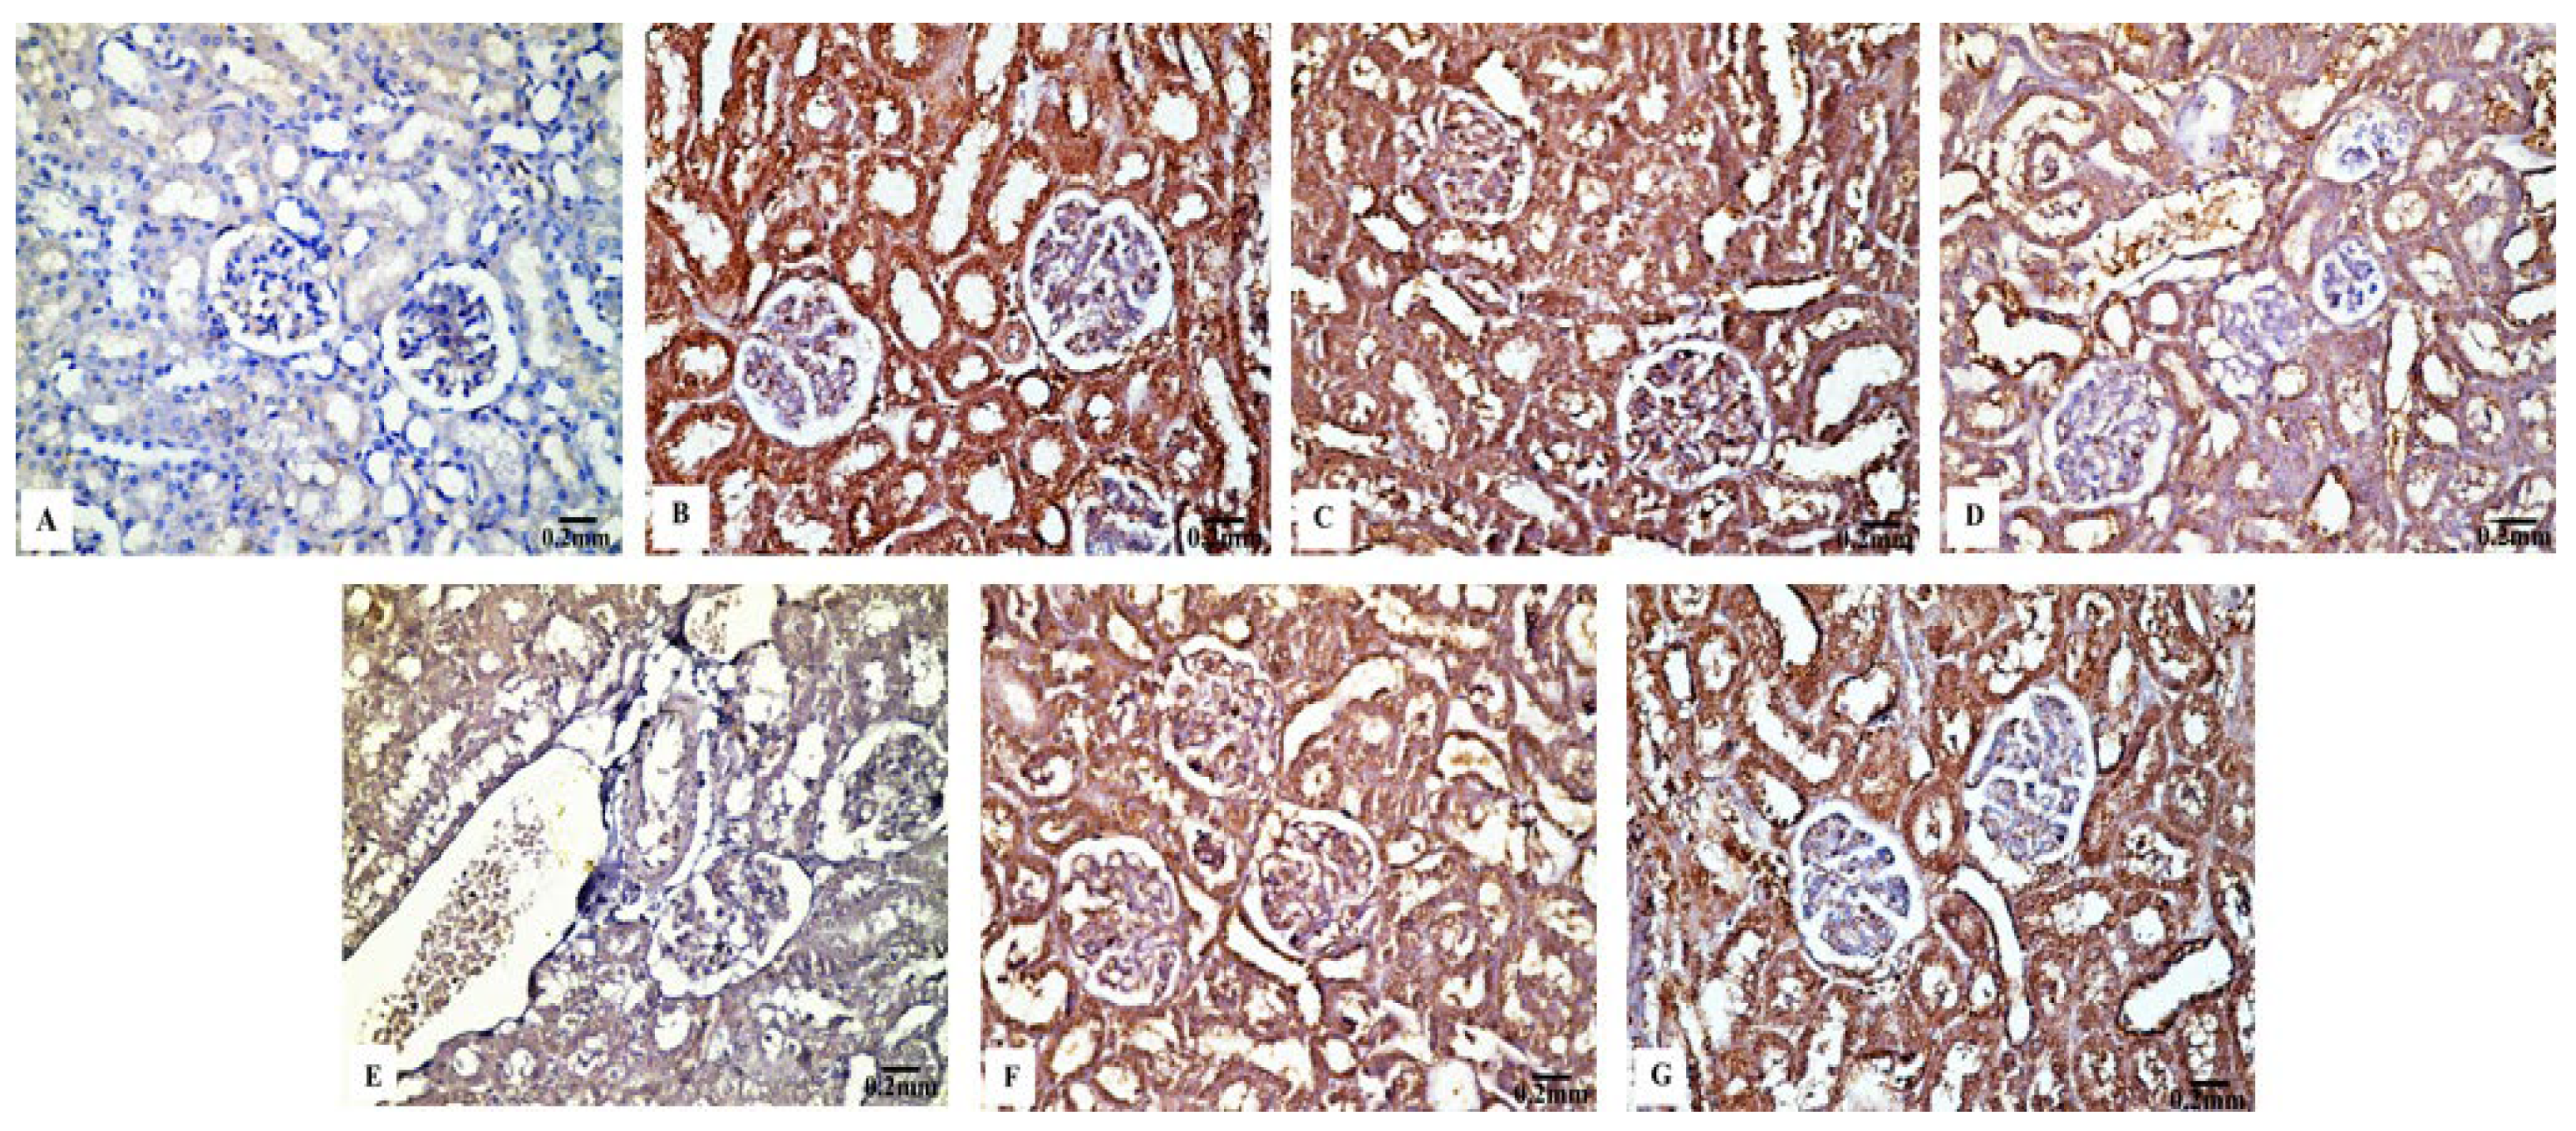

3.4. Immunohistochemical Results

3.4.3. Cas3 Immunoreactivity

3.4.4. TNF-α Immunoreactivity

4. Discussion